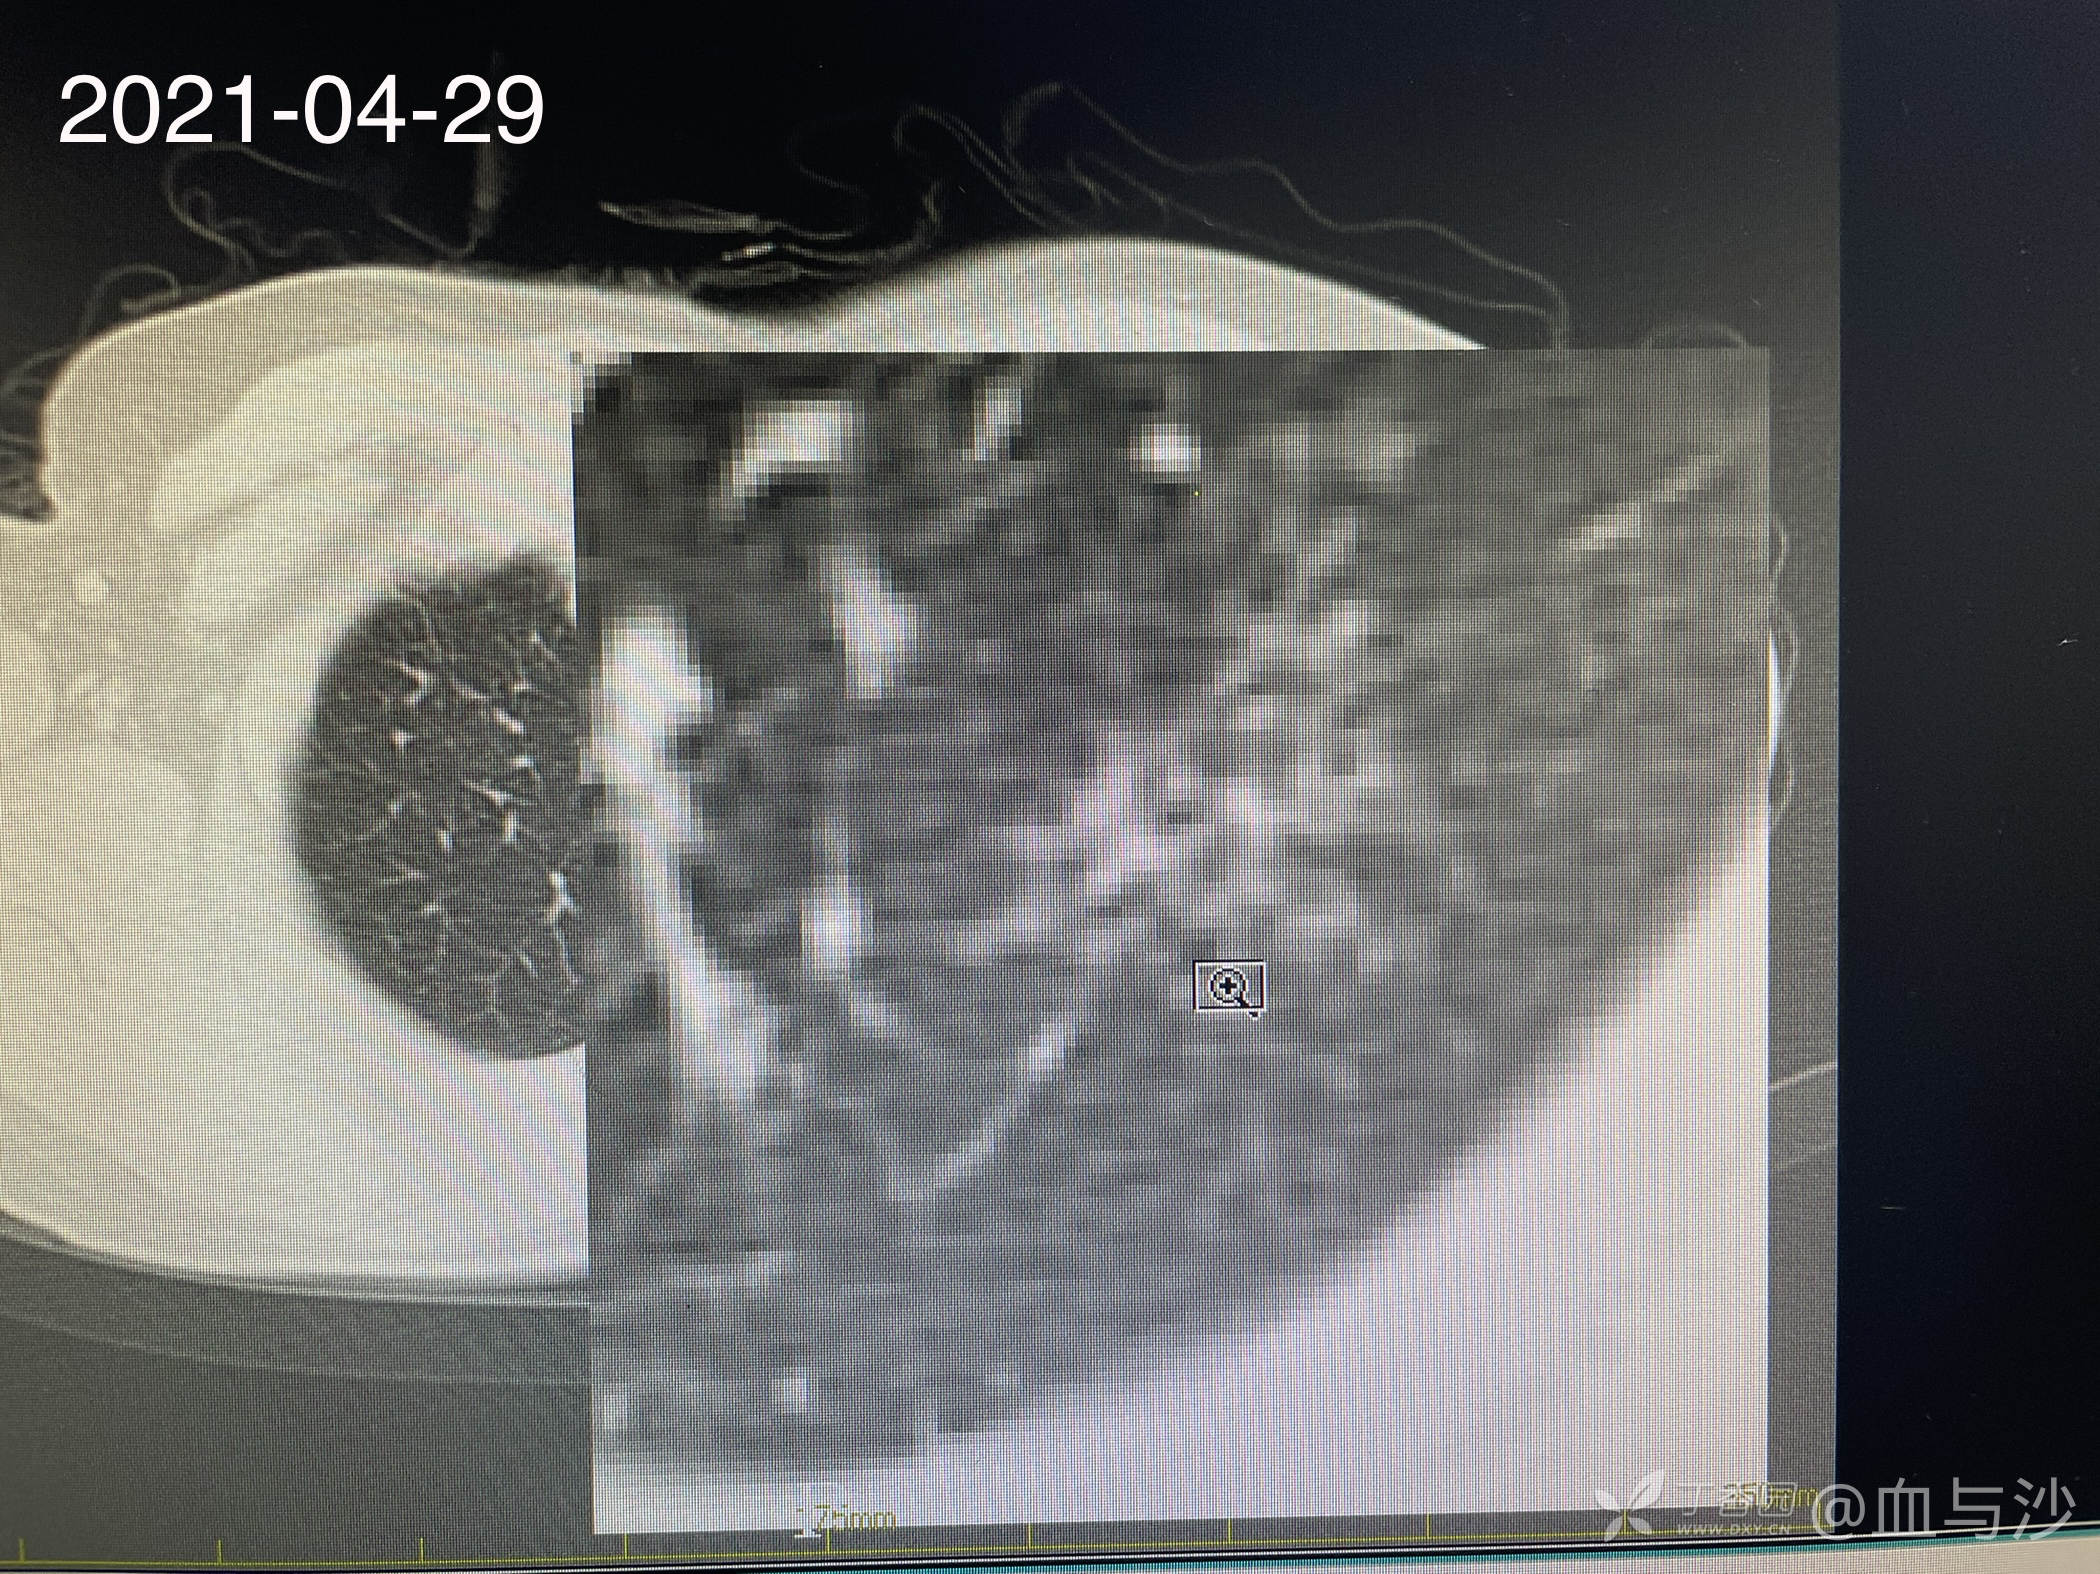

病人女,60岁,去年4月底因咳嗽发热入院,诊断支气管扩张伴感染(结核各项检查阴性,病人平时也无潮热盗汗),予抗感染对症处理。当时CT片左肺上叶有一磨玻璃样影。今年5月病人再次咳嗽发热入院,续按照支扩伴感染处理,但CT显示去年的磨玻璃影成了一约1.5cm的实性结节。